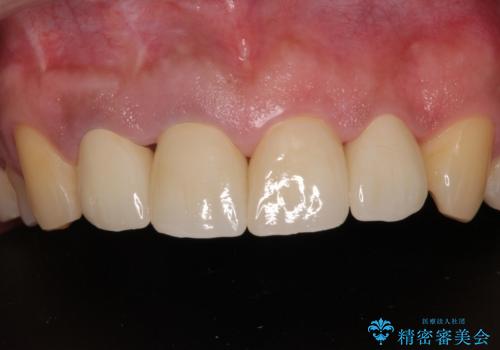

前歯の審美歯科治療 下顎の部分矯正と上顎前歯のオールセラミッククラウン

- 前歯の見た目を気にして来院された患者様です。

痛みが消えた後に、より目立たない装置をご希望とのことで、下顎前歯の舌側矯正で部分矯正を行い、歯列が整い、上顎前歯歯根部の病変が消退したことを確認した上で、上顎前歯をオールセラミッククラウンにて補綴治療を行うこととしました。

前歯部の見た目を改善するために、様々な医院を巡られたそうですが、当院ご提案のプランにて、痛みもスッキリと引いた、満足のいく仕上がりとなりました。